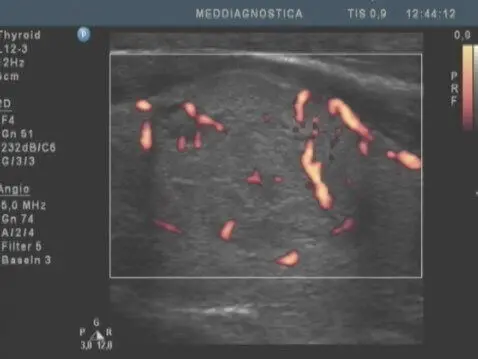

УЗД щитовидної залози. Один і той же пацієнт, дослідження щитовидної залози з інтервалом в 3 роки, збільшення вузла з розмірів 11х7х10 мм до 26х17х19 мм. Освіта визнано доброякісним. (Різниця в кольорі знімків – розрив апарати)